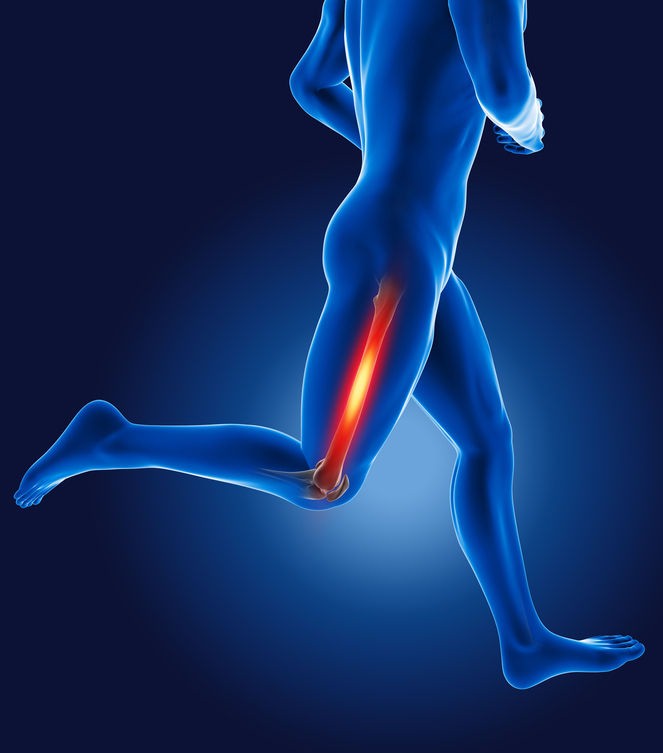

شکستگی استخوان ران (فمور) در سه ناحیه اتفاق میافتد: سر/ گردن استخوان (سر فوقانی استخوان نزدیک لگن)، بدنه اصلی استخوان یا سر پایینی استخوان نزدیک زانو. استخوان زمانی میشکند که ضربهای شدید به استخوان ران وارد شود. عامل ایجاد این ضربه ممکن است وزن بدن بیمار، برای مثال هنگام زمین خوردن، یا اصابت اشیاء، مانند زمان تصادف، باشد. شکستگی استخوان ران که به صورت ترکهای ساده و کوتاه باشد، معمولاً نیازی به جراحی ندارد.

استخوان ران در آسیبدیدگیهایی با انرژی بالا، مانند افتادن از بلندی یا تصادف وسایل نقلیه موتوری میشکند. بیماران دچار پوکی استخوان، عفونت یا تومور استخوان یا با سابقه تعویض مفصل زانو بیشتر در معرض شکستگی استخوان ران قرار دارند. استخوان ران سالمندان حتی در اثر به زمین افتادن از حالت ایستاده نیز میشکند، چرا که استخوان معمولاً به موازات افزایش سن ضعیف و شکننده میشود. اگر شکستگی پیآمد آسیب دیدگی باشد، پس از ثابت نگهداشتن استخوان و جوش خوردن آن از طب فیزیکی برای افزایش دامنه حرکتی زانو و مفصل ران، تقویت و آموزش شیوه گام برداشتن صحیح بهره گرفته میشود. جهت اطلاعات بیشتر از انواع روشهای ورزش درمانی، مزایای ورزش درمانی و تأثیراتی که میتواند در سلامت فرد داشته باشد میتوانید با متخصصین کلینیک ما در ارتباط باشید. برای اطلاعات بیشتر با شمارههای 03136252857 تماس حاصل فرمائید.